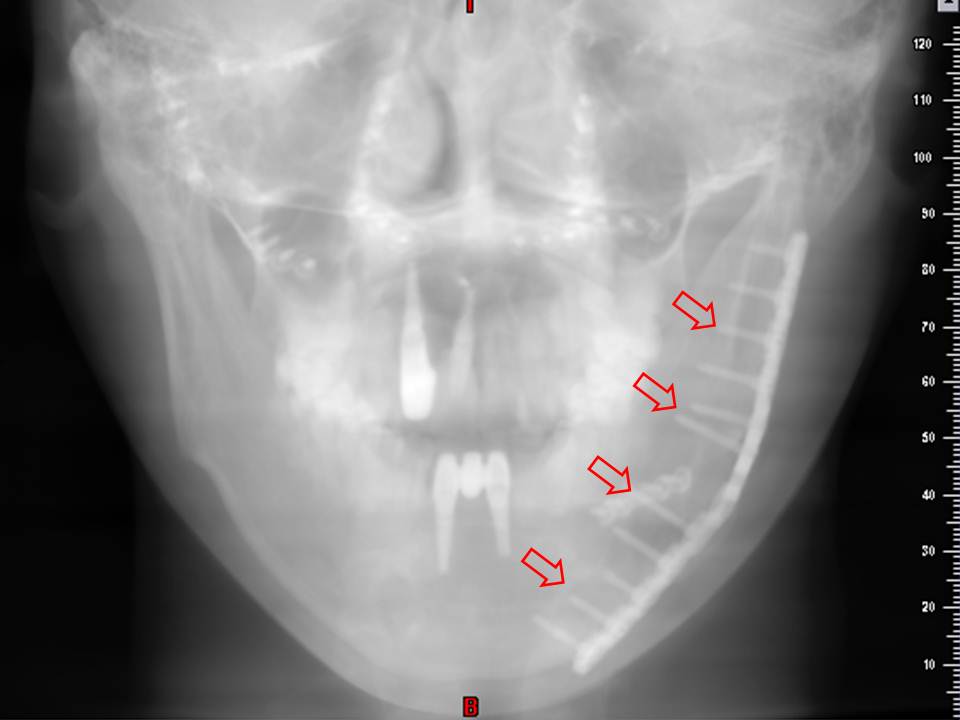

我們來看一些實際的案例。上圖左邊手術後一週的骨頭,

還可以明顯見到切開過的縫隙以及交界處的不平整,

但是右圖可見一年之後的骨骼癒合得相當理想,

所以絕大多數的情況下都不必擔心手術後的骨骼強度不足。